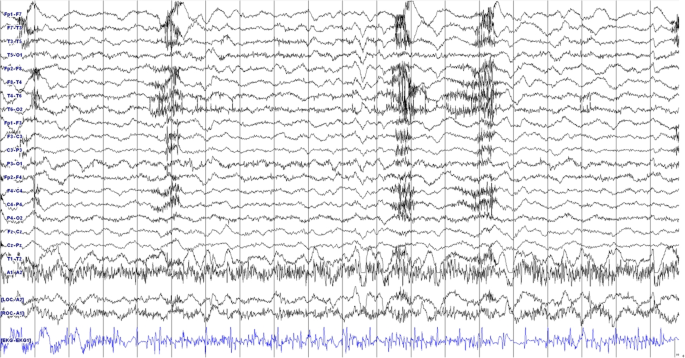

Figure 1 on presentation, she was drowsy and vital signs were as follows: blood pressure, 125/65 mmHg; body temperature, 36.4 °C; pulse rate, 100 per minute; respiratory rate, 19/min. The emergency medical faculty immediately gave her intravenous LEV 1000 mg; however, there was one more generalised tonic-clonic seizure without mental recovery. Video-EEG monitoring was initiated 2 h after the end of LEV loading; at that time, she started to show choreoathetoid movements in her face and bilateral limbs (see Additional file 1), but no epileptiform discharges were noted on concomitant electroencephalography (EEG) as seen in Fig. 2. Laboratory findings including complete blood counts, electrolytes, blood urea nitrogen, creatinine, and arterial ammonia levels were normal. Review of her medical history revealed that she had been treated with solifenacin, esomeprazole, baclofen, and escitalopram for more than 3 months. She was not on concomitant drugs such as dopamine receptor blockers or antipsychotic agents. Considering the temporal relationship between the onset of involuntary movements and administration of LEV, further treatment with LEV was withheld. Chorea movement continued for about 30 min. She could communicate with her caregiver and physician until the end. After administration of 4 mg of lorazepam and 1200 mg of phenytoin, the involuntary movements ceased gradually. The next day her mental status gradually improved and no more involuntary movements were observed.

For a seizure originating from mesial temporal lobe and not propagating to lateral structures, the EEG could be negative. However, she was able to communicate while showing the movements, unlike mesial temporal lobe seizures in which consciousness is usually impaired. Moreover, a majority of automatism seizures lasts for less than 1–2 min. Even though we suppose that she was in a complex partial status epilepticus (CPSE), her ongoing movement did not accompany any epileptiform discharges nor clinically evolving features for a relatively long time during video-EEG monitoring, which does not meet the commonly used diagnostic criteria for CPSE. Use of benzodiazepines can alleviate or terminate not only epileptic seizures but also involuntary movements such as tremor, chorea, and dystonia. However, a possibility remains that her symptom was a mesial temporal lobe seizure with oromandibular and manual automatisms because cessation of the movement was observed after administration of other AEDs.